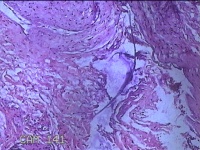

右侧髋部结节

性别

女

年龄

50岁

临床诊断

皮下结节

一般病史

发现右髋部结节1个月余。

标本名称

大体所见

灰白粉红色结节1.3x0.5x0.2cm一个,表面光滑,切开结节呈实性,切面灰白粉红色,质软。

有的地方感觉像个血管瘤,未见明确恶性